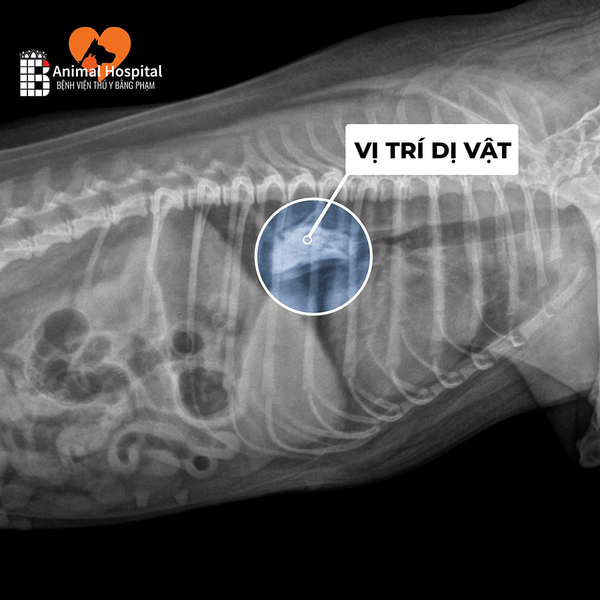

Công nghệ này giúp phát hiện tổn thương nội tạng, xương, khối u, hoặc dị vật với độ chính xác cao, hỗ trợ bác sĩ đưa ra phác đồ điều trị hiệu quả nhất.

- Khi khảo sát các vùng như hộp sọ, xoang mũi, tai trong, lồng ngực, ổ bụng – nơi siêu âm hoặc X-quang không đủ chi tiết.

- X-quang (X-ray) phù hợp để kiểm tra nhanh các vấn đề xương gãy, viêm phổi, hoặc nuốt dị vật

🔍7. Hình Ảnh Thực Tế – Kết Quả Sau Khi Chụp

Hình ảnh CT thể hiện chi tiết từng lớp cấu trúc trong cơ thể, giúp bác sĩ:

- Xác định chính xác vị trí khối u, ổ áp xe, hoặc chấn thương sâu.